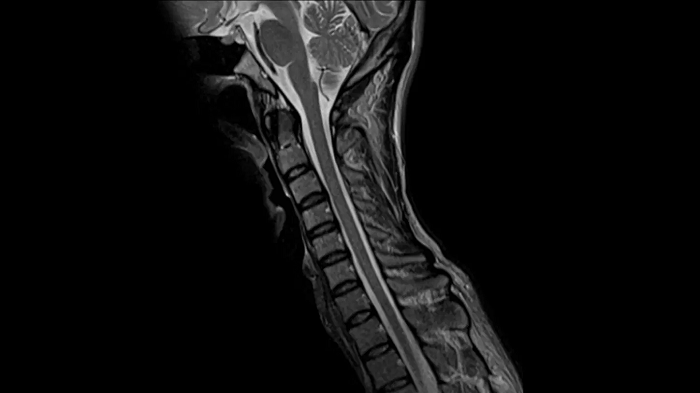

Spine

T2 TSE

Exceptional C-Spine images with T2 TSE with the use of the Head/Neck coil.

Deep Resolve Gain & Sharp

0.5 x 0.5 x 3.0 mm2

TA 3:28 minutes

MAC-ID: 7aaaa0164.

MAC-ID: 7aaaa0164. Image Credit: Siemens Healthineers